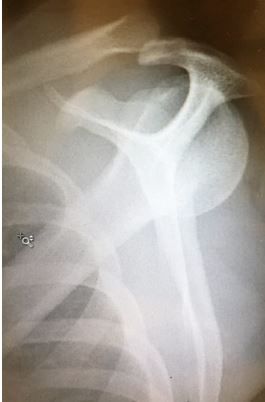

Testing: X-rays of the knee and femur are normal. X-ray of the left shoulder is shown below.